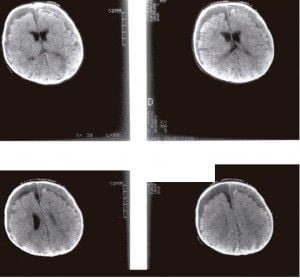

Hematoma subdural bilateral que se extiende en

el espacio interhemisférico (TC sin contraste).